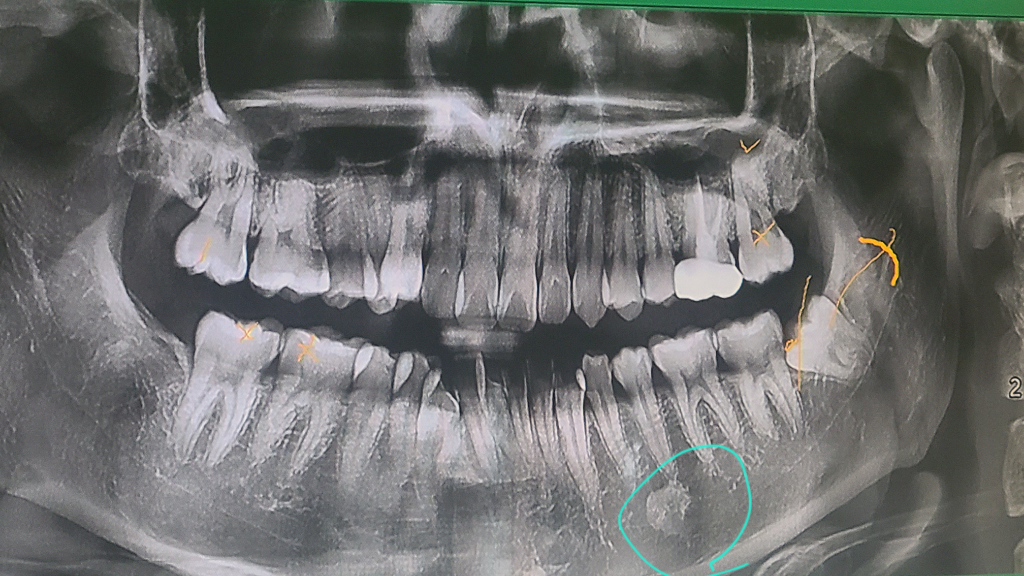

사랑니 뽑으러 간 치과에서 찍은 시티에서 우연히 발견한 골내병소 소견을 가지고 대학병원 치과에 가서 엑스레이와 하악 CT를 촬영하니 뼈가 팽창하거나 그런 건 안 보인다고 1년 뒤에 다시 오라 하셨고, 아마 1-2년 정도 관찰하고 이상없으면 쭉 괜찮을 거라는데 진단명이 선천성 하악 골경화증이었습니다 혹시 이게 발생하는 이유와 예후에 대해서 알려주실 수 있을까요? 암이 되거나 그러진 않겠죠...?괜시리 염려되어 여쭤봅니다

사랑니 뽑을 때 찍은 ct 첨부합니다